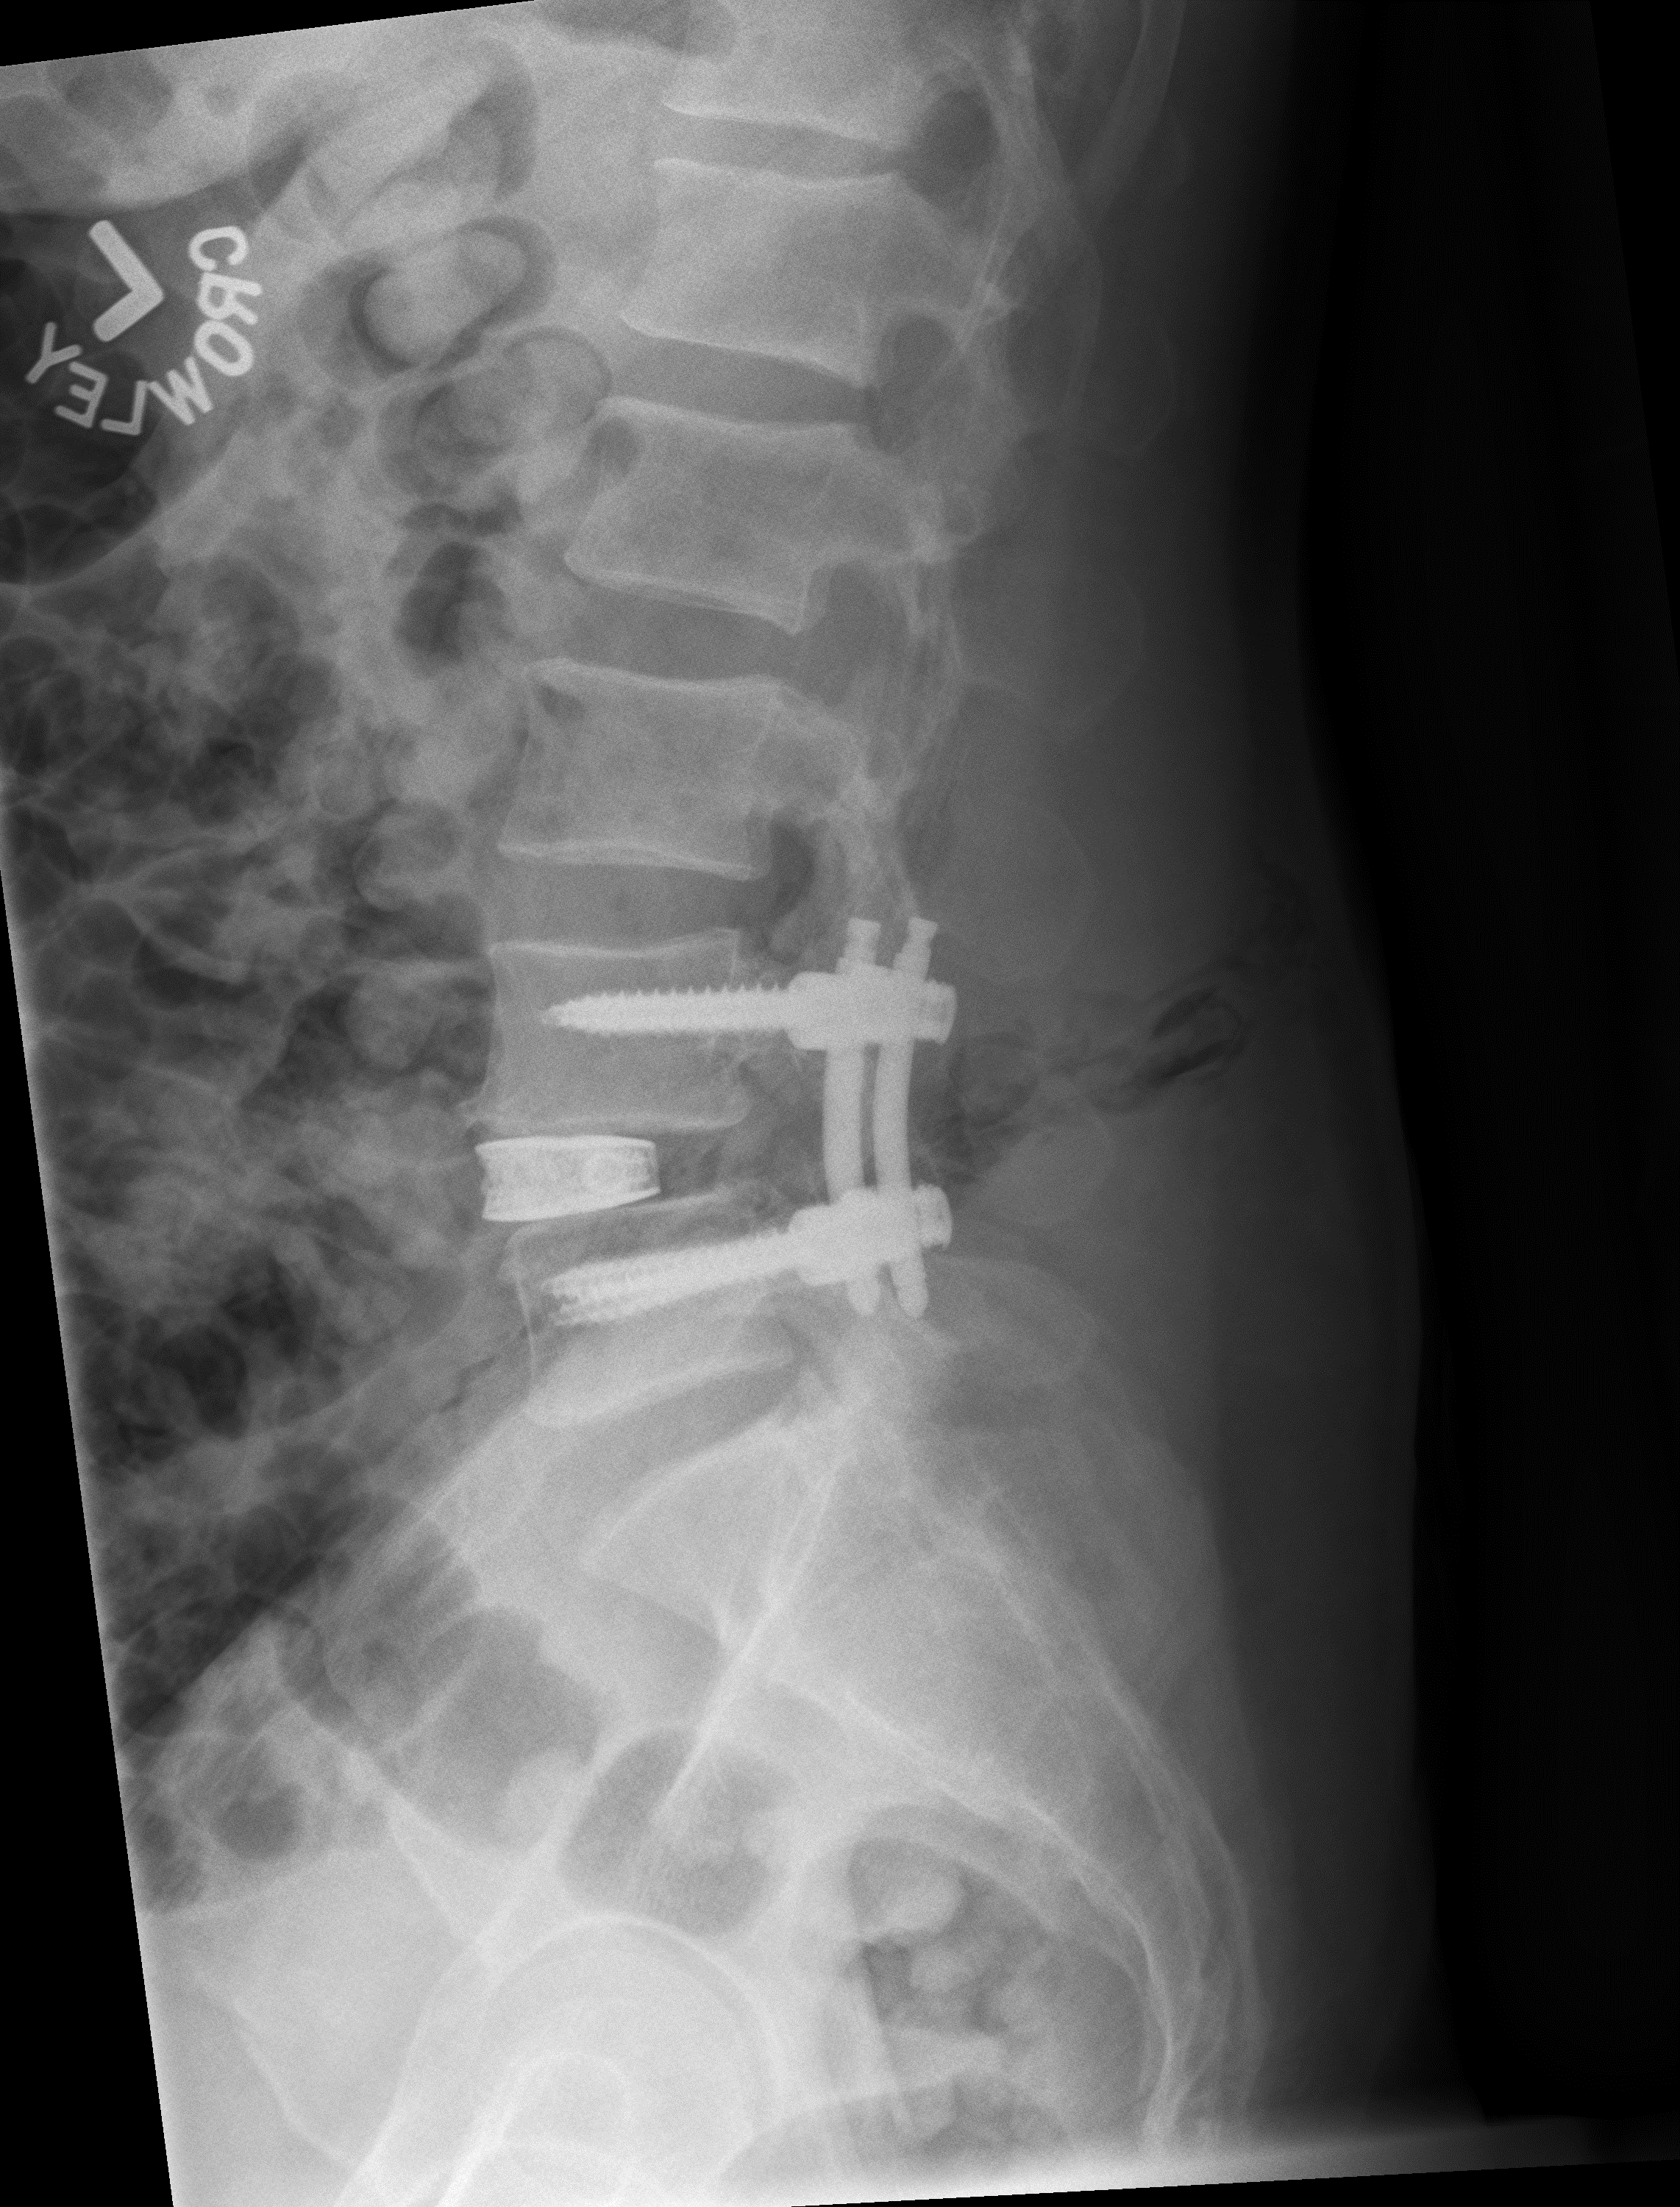

Alignment restored after surgery.png

I tell everyone I feel like Superman,” he said. “I had all of the faith in the world that Dr. Bennett could do it. And even at the hospital, he took the time to give my wife a call during the procedure to let her know how I was doing. He sees surgery from his side, but also from the family side.”

— John Helper